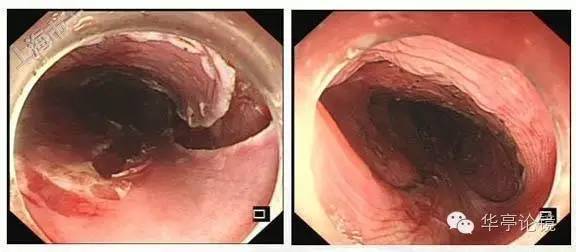

ME-NBI内镜:病变明显处分支血管网消失,IPCL呈IV-V1型改变为主,部分区域呈V2型改变。部分区域粘膜表层糜烂,表浅血管显露(绿色框内)。

2016年6月7日,病人行ESD术,术顺,以下为完整切除标本。

切除完整标本送检,20160614病理:(食管)粘膜糜烂伴部分区鳞状上皮高级别上皮内瘤变,水平、垂直切缘均未见肿瘤累及。